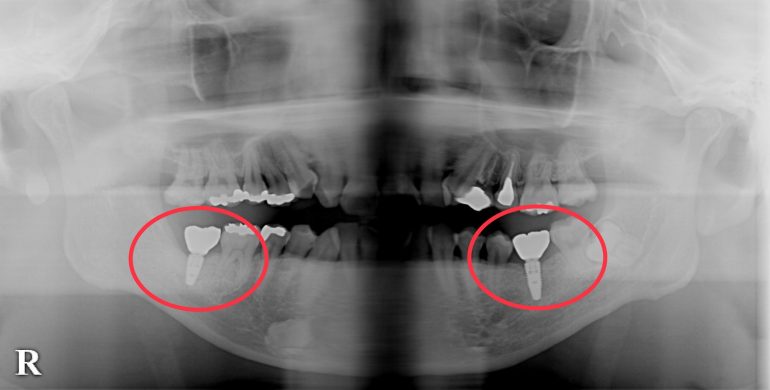

当院インプラント患者様のビフォー、アフターのレントゲン写真です。

Before

抜歯後入れ歯を作成しましたが使用しなくなっていたため院インプラント治療を受けられました。

After (1年後)

Before

抜歯後入れ歯を作成しましたが使用しなくなっていたため院インプラント治療を受けられました。